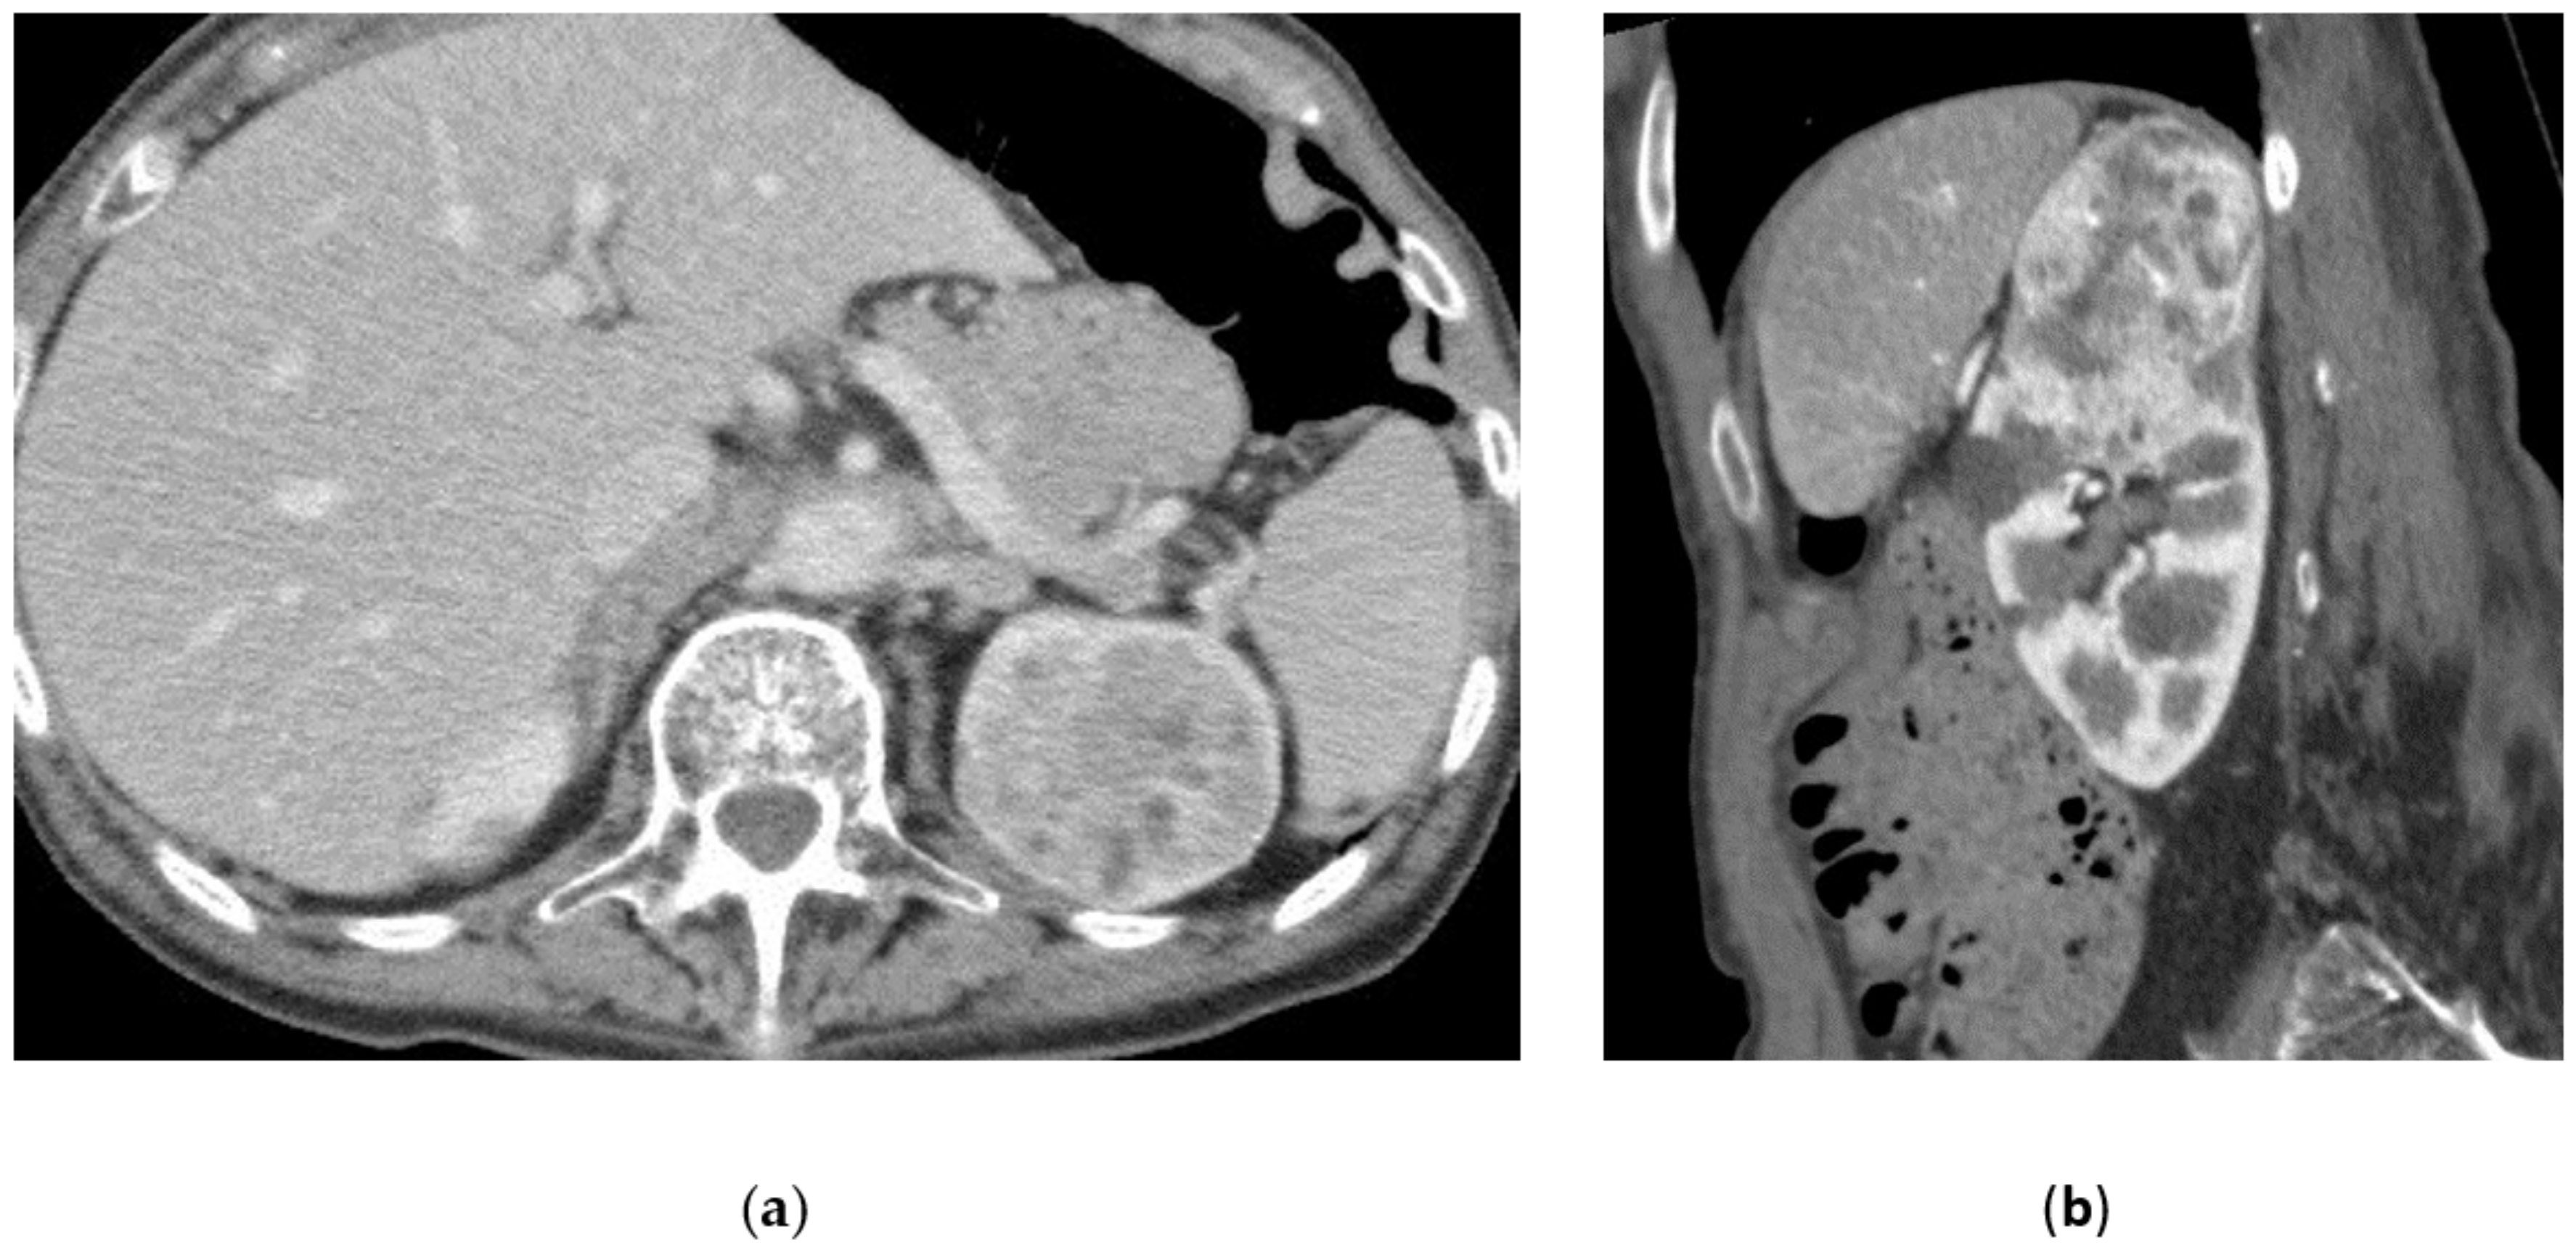

3.5. Renal Angiomyolipoma

3.6. Malignant Renal Tumors